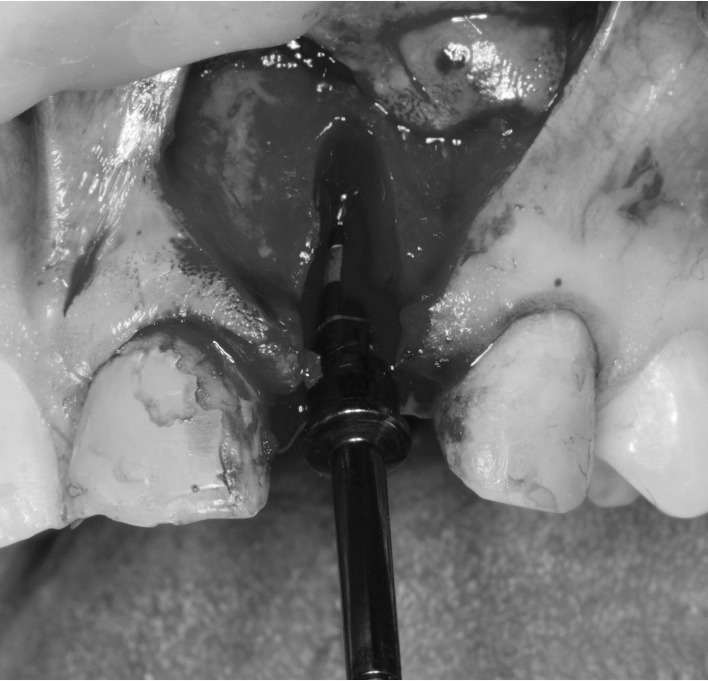

Пациентка дала письменное согласие на проведение всех процедур. Удаление зуба было выполнено атравматично с помощью люксаторов. Был сформирован лоскут. Немедленная установка имплантата была проведена одновременно с направленной костной регенерацией (GBR) без кортикотомии и без пластики мягких тканей (так называемая «техника Бургера» по Urban и соавт.).

Процедуры установки имплантата и GBR прошли без осложнений; первичная стабильность имплантата составила 35 Н·см (Dentium Implantium 3.5 мм × 10 мм). GBR проводилась с использованием смеси аутогенной кости и частиц Bio-Oss® (Geistlich), а также мембраны Bio-Gide (Geistlich). Область операции была ушита швами Prolene 6/0. Во время операции не было отмечено признаков избыточного кровотечения, характерного для повреждения сосудов.

Интраоперационный вид. Подготовка ложа под имплантат после удаления верхнего левого латерального резца. Чрезмерного кровотечения во время операции не наблюдалось.